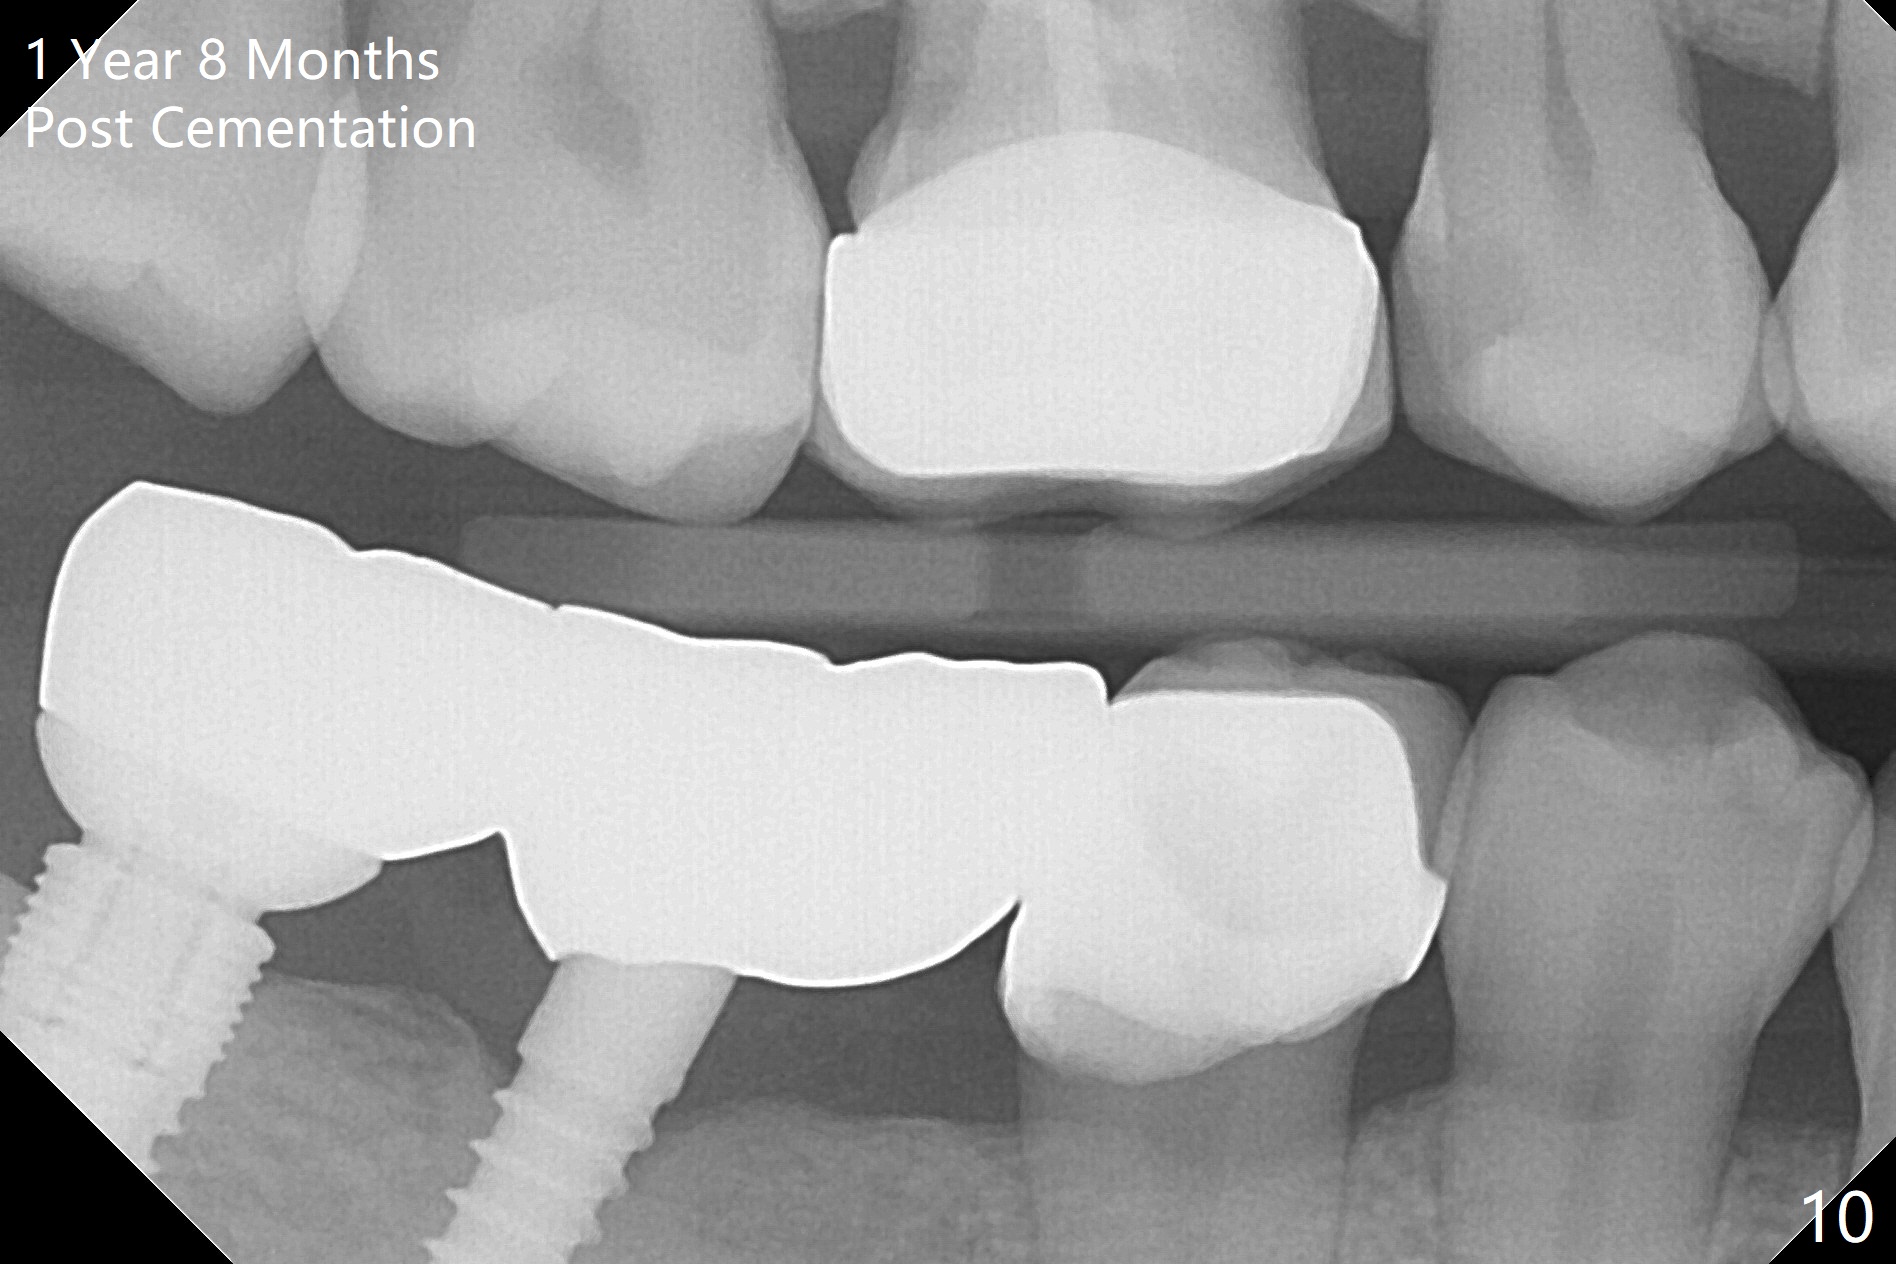

The patient returns for final restoration 3 months postop; bone resorption around the 1-piece implant is minimal (Fig.7).  The definitive restoration is also splinted.  The latter is further justified when the implant at #30 is found to be distal prior to cementation (Fig.8 *).  It appears that implant spacing at the root level is more critical than parallelism, as compared to Fig.7.  Let us improve this aspect.  Bone loss around the implants remains minimal 7 months post cementation (Fig.9).  It is the same 1 year 8 months post cementation (Fig.10), as compared to a cantilever FPD on the other side (Fig.11).  The bone density around the implants at #30 and 31 increases 2 year 8 months post cementation (Fig.12).